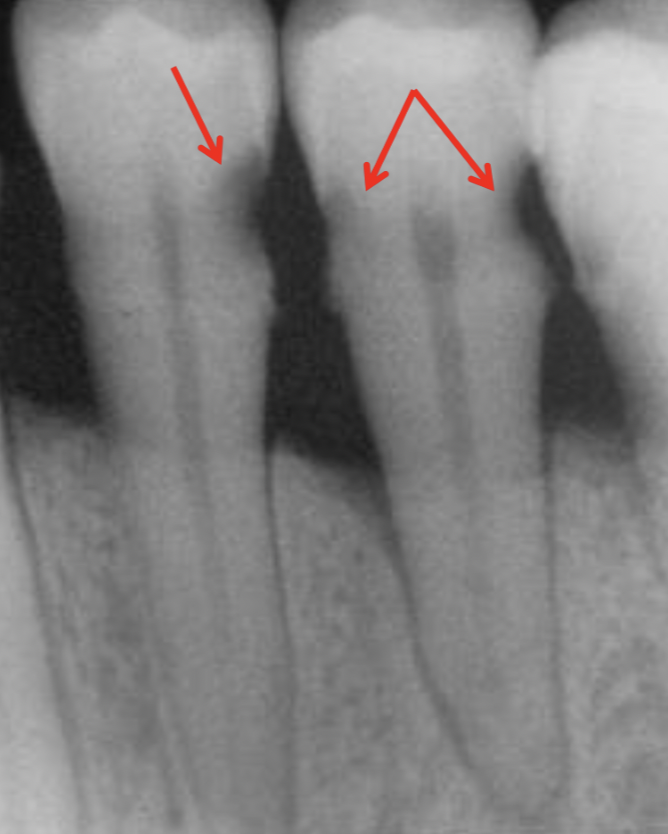

Q

A

initial caries (IC)